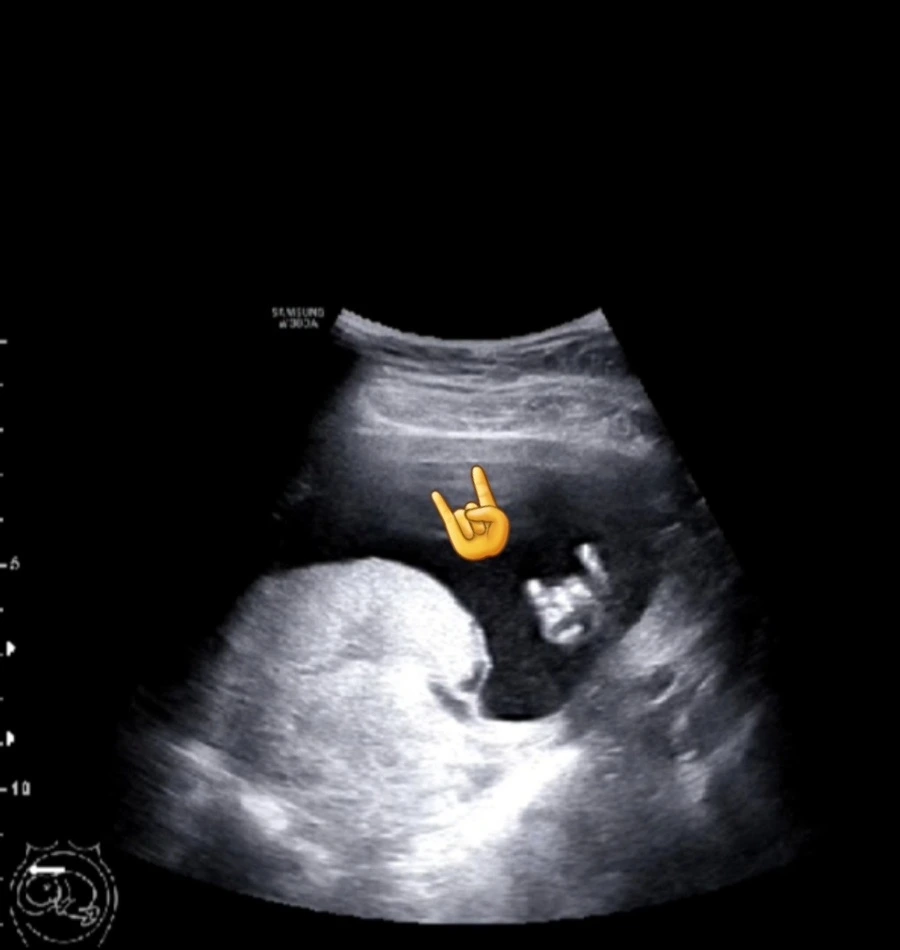

아기의 발바닥과 peace를 날려주고 있는 아기의 손가락

남편도 이 날 초음파를 보면서 개념적으로만 알던 아기의 존재를 움직이고 살아있는 존재로 만나니 정말 아빠가 된 듯한 느낌이었다고 말했다. 모든 것이 정말 정말 신기했다. ’반짝아, 너 정말 거기에 있구나!ㅎㅎㅎ 모든 것이 처음인 엄마와 아빠는 너가 양 손을 들어 올려 얼굴을 가리고 손을 흔들 흔들 하고 있는 모습에 반했어. 너무 신기한거 있지? 손가락을 빨기도 했다가, 마지막에는 peace를 하며 손가락을 오므린 너의 모습을 보면서 감동의 감동을 했다!’